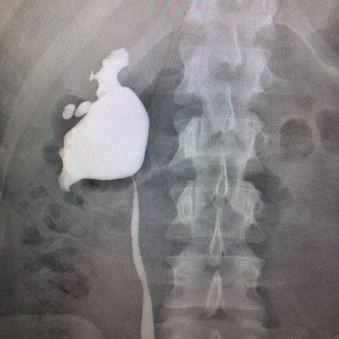

Renal arteriogram

A renal arteriogram is a special type of X-ray picture that helps doctors see the blood vessels in your kidneys.